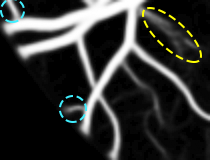

4.6 Robustness to the Inter-Rater Variability

The manual annotations provided by physicians are crucial for training and testing supervised methods. Experience may help experts refine their segmentations, but two different observers will always have their own way of approaching the task. There is not always agreement between the experts since some of them systematically see more vessels than others. Moreover, even when the vessel is clear, differences in the estimation of its caliber may arise. For these reasons, inter-rater variability is always present in the evaluation process. Here, we discuss how this variability affects the obtained results.

All the previous results reported in this work were obtained using the annotations of the first human observer as the gold standard for training and testing. In Table 7, otherwise, the gold standard, for testing, were the annotations of the second human observer. Having these as ground truth, we then compared both the first observer and the model, for each database. Regarding the tests of statistical significance, we aimed to reject the following null hypothesis: the results of the Proposed method are not statistically different from those of the first human observer.

As shown in Table 7, if we consider the second observer as the gold standard, the model outperformed the first observer regarding Sp and Acc, in the STARE and CHASE_DB1 databases. According to the definition of Sp, this means that it introduced fewer false positives than the first observer himself (in relation to the second one). In other words, some of the pixels marked as background by the model, and rejected by the first observer, ended up being validated by the second one. In the DRIVE database, the model performed better than the first observer in terms of Sn, Sp, and Acc. This shows that apart from having less false positives, it also presented less false negatives than the first observer. That is, even though the model was trained according to the first observer, it could identify vessel segments that only the second observer saw. Together, the previous results suggest that even when the model was trained according to the first observer, it seemed to be more consistent than him when another observer was considered. To put it another way, the differences established between two independent human observers appeared to be higher than those presented by the model when it was evaluated against a new reference. This reveals a consistency which may be unreachable to a human who always oscillates from day to day and can be affected by fatigue or stress.

Comparing Tables 5 and 7, we can further analyze how the model behaved when we changed the reference from the first to the second observer. For the STARE and CHASE_DB1 databases, the average Acc of the model fell from 0.9694 and 0.9653 to 0.9365 and 0.9600, respectively. This means approximate decreases of 3.4% and 0.5%, which sound natural since it was trained according to the first observer. For the STARE database, in particular, the decrease was higher since the second observer systematically marks more vessels than the first one. The DRIVE database case was surprising. The average Acc rose from 0.9576 to 0.9639, which corresponds to an approximate increase of 0.7%. This means that despite being trained according to the first observer, the model was closer to the second one.

Except for the STARE database, in both the remaining databases there is no clear difference between the marking pattern of the experts. That is, we can see cases where the first observer marks vessels that the second one does not see and vice versa. This may be deduced from Fig. 7, where we compare the annotations of both observers, for each database. We believe that this noticeable discordance may become a limiting factor for future improvements since the current results of this field are already extremely accurate.